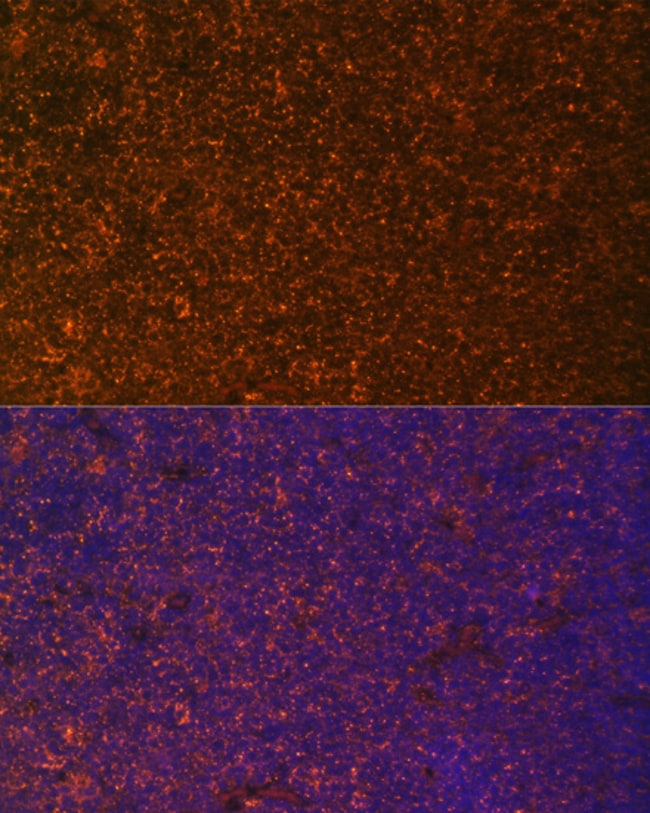

Invitrogen™ DR3 Polyclonal Antibody

Immunogen sequence: QGGTRSPRCD CAGDFHKKIG LFCCRGCPAG HYLKAPCTEP CGNSTCLVCP QDTFLAWENH HNSECARCQA CDEQASQVAL ENCSAVADTR CGCKPGWFVE CQVSQCVSSS PFYCQPCLDC GALHRHTRLL CSRRDTDCGT CLPGFYEHGD GCVSCPTPPP SLAGAP Positive Samples: Raji, HT-29, U-87MG, A-549; Cellular Location: Cell membrane, Single-pass type I membrane protein.

ELISA, Western Blot